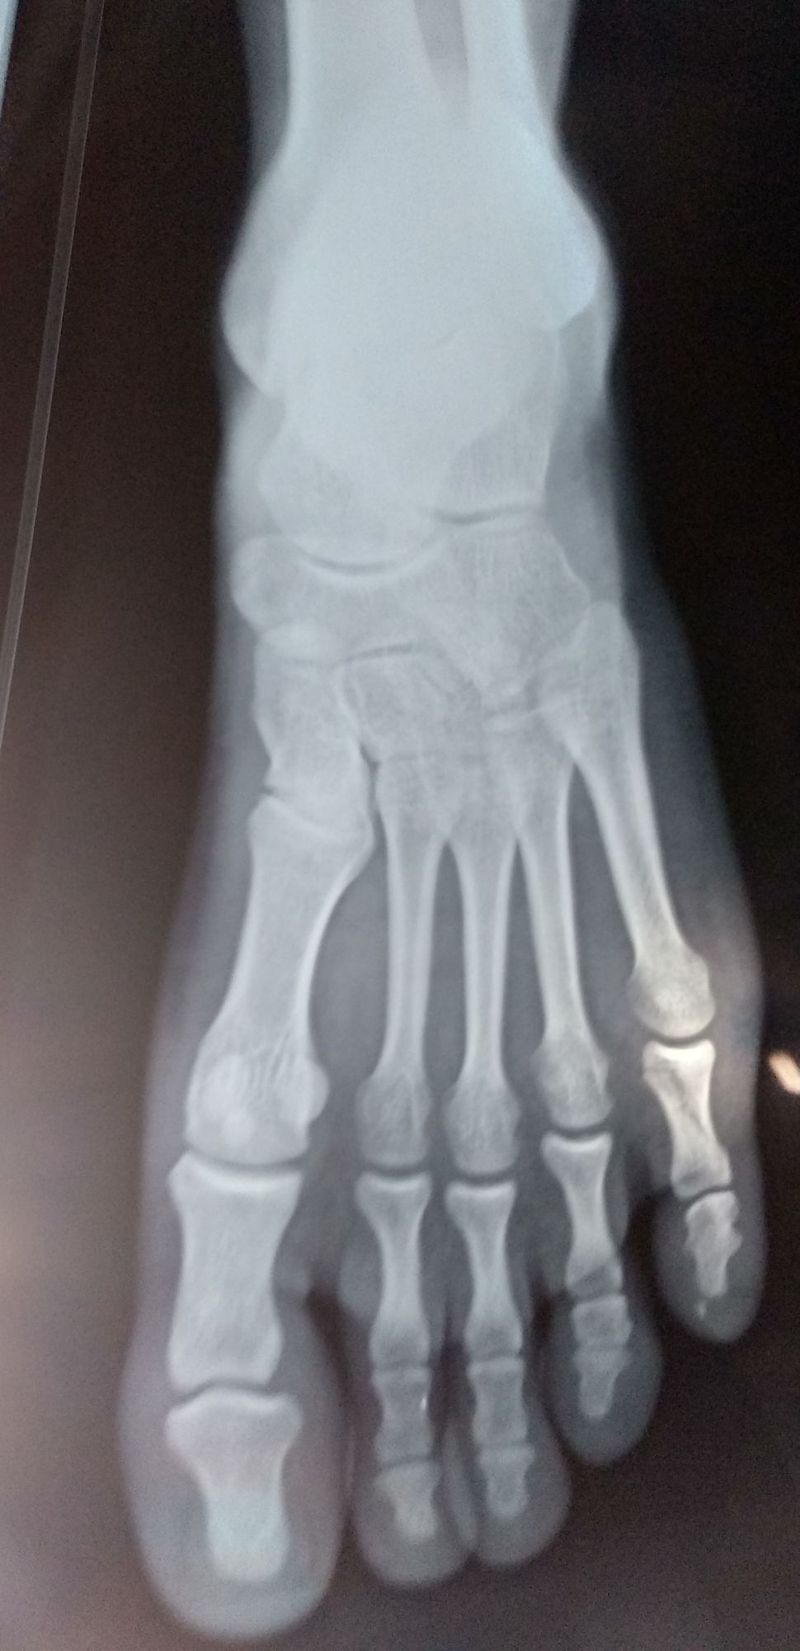

Diagnose the case

Bones

Foot

Orthopedics